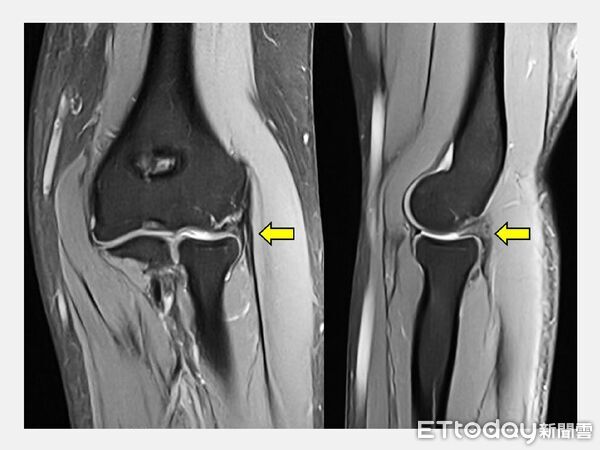

陳重宇指出,理學檢查及核磁共振(MRI)顯示,C小姐除了肱骨外上髁炎外,還伴隨肘關節滑膜皺襞增生與軟骨軟化。這類結構性問題若只以一般「網球肘治療方式」處理,往往難以真正解除疼痛來源,反覆發作也就成了常態。

▲術前MRI顯示滑膜皺襞增生,擠壓肘關節軟骨造成發炎。(圖/記者游瓊華翻攝)